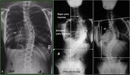

Her bir tür, farklı tedavi yaklaşımları gerektirebilir. İdiyopatik skolyoz, genellikle ergenlik döneminde ortaya çıkar ve tedavi edilmediğinde ciddi sorunlara yol açabilir. Skolyozun TanısıSkolyozun tanısı genellikle fizik muayene ve görüntüleme yöntemleri ile konur. Doktor, hastanın duruşunu değerlendirir ve gerekirse röntgen çekimi yapar. Röntgen, omurganın eğilimini ve açılarını belirlemeye yardımcı olur. Skolyoz Tedavi YöntemleriSkolyoz tedavisinde kullanılan başlıca yöntemler şunlardır: